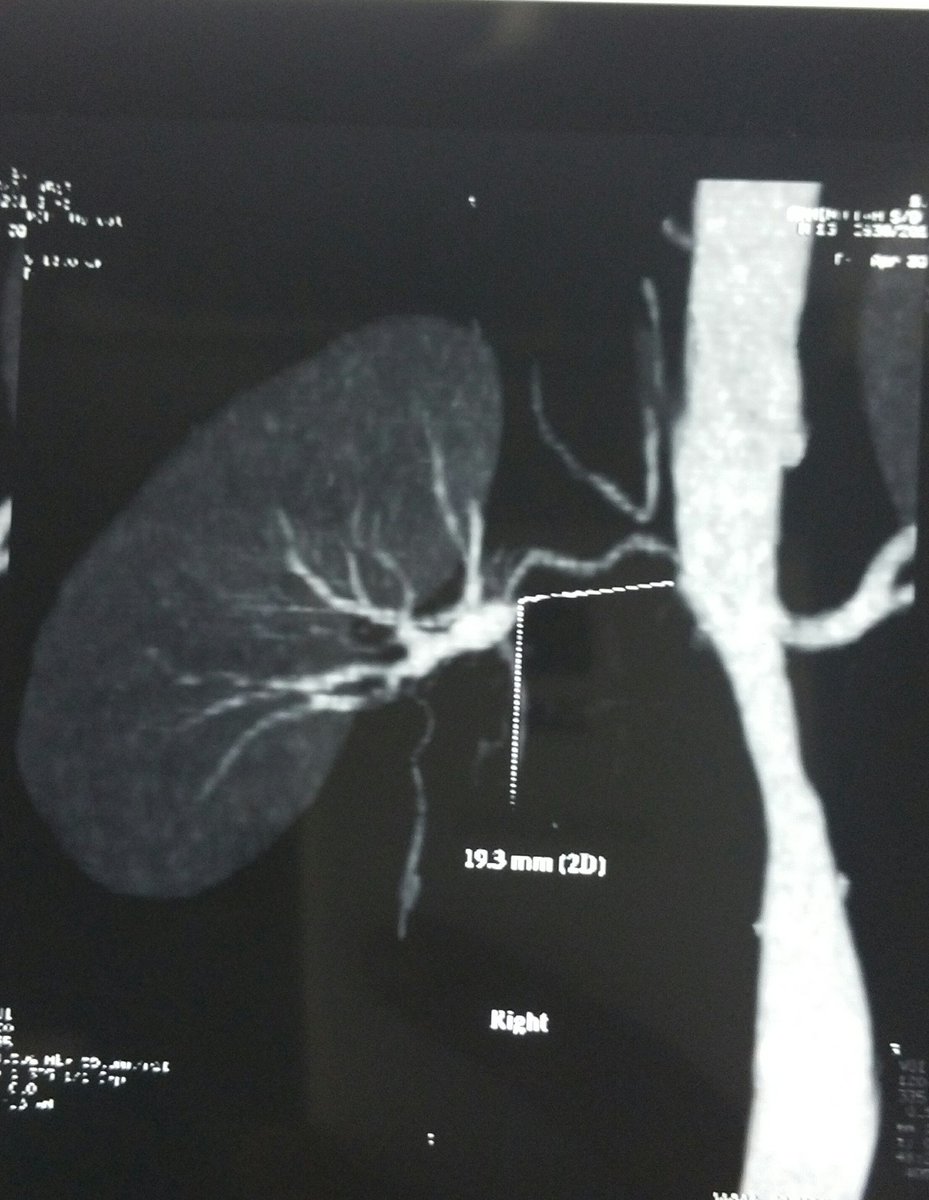

Renal artery stenosis " Surgical cause of Hypertension " 13 years old male evaluated for uncontrolled HTN

#CTangio#RAS#Elevated_Reninpic.twitter.com/HfneqQRH62